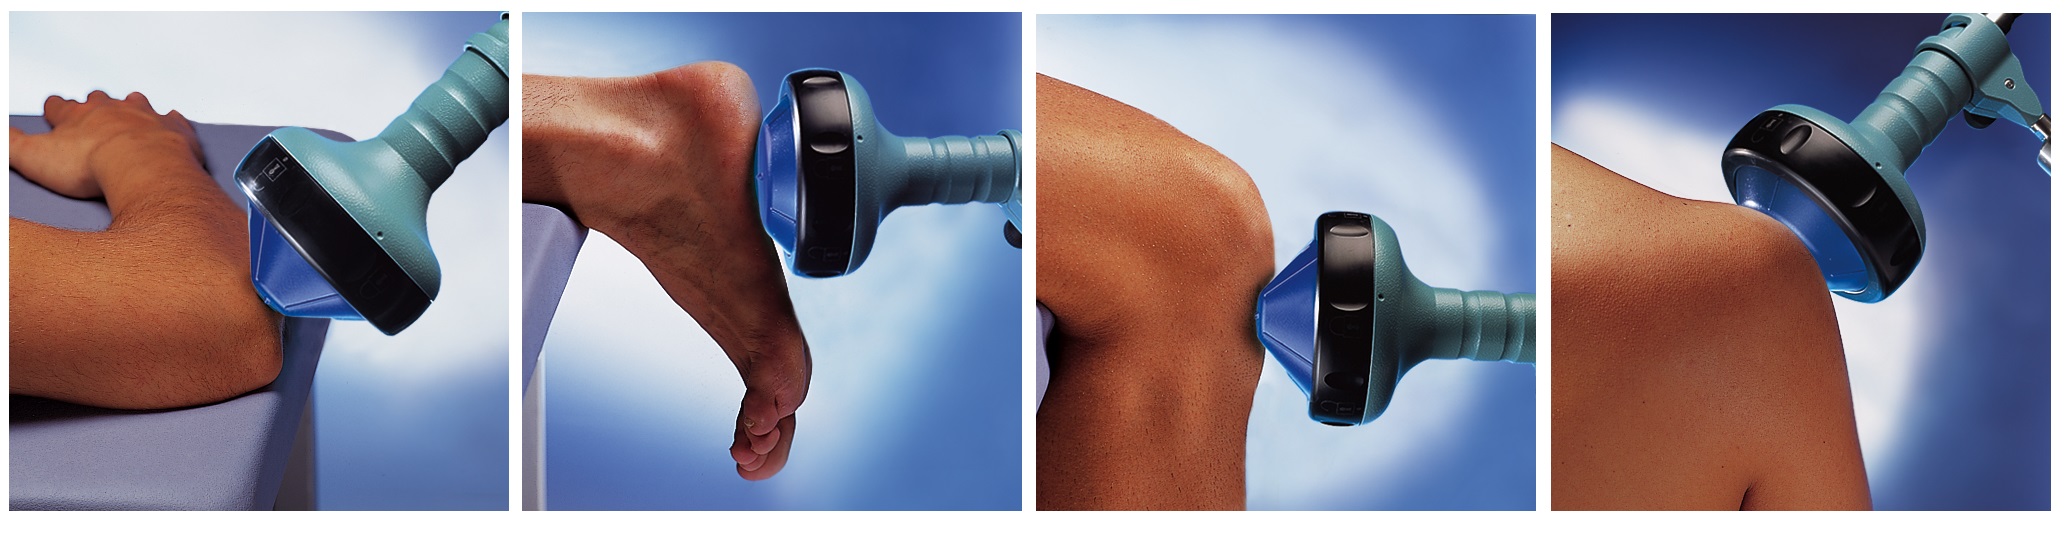

Экстракорпоральная ударно-волновая терапия доказала свою эффективность при лечении следующих заболеваний опорно-двигательного аппарата:

эпиконделит плечевой кости

подошвенный фасциит, в том числе "пяточная шпора"

тендинит сухожилия четырехглавой мышцы бедра ("колено прыгуна")

псевдоартроз

синдром Дюпюитрена

плечелопаточный периартроз

- и другие распространенные заболевания опорно-двигательного аппарата

Использование сфокусированной ударной волны для проведения терапии триггерных точек позволяет уменьшить или ликвидировать болевой синдром без применения фармакологических препаратов, а также в случае их неэффективности.

лечение связок надколенника (синдром головки надколенника)

лечение подошвенной фасции при подошвенном фасциите с пяточной шпорой

лечение мягких тканей в области головки плечевой кости с и без кальцифицированного тендиноза

локтевой эпикондилит плеча ульнарный и радиальный у тениссистов и гольфистов

индурация полового члена (болезнь Пейрони)

Показания для УВТТТ:

Показания для УВТТТ:

Аппарат ударно-волновой терапии ПьезоСон 100 Плюс от RICHARD WOLF GmbH объединяет в себе и демонстрирует уникальный пример показаний к УВТ в ортопедии с применением УВТТТ. Это означает существенное расширение сферы применения в большой области миофасциального болевого синдрома.

Экстракорпоральные сфокусированные ударные волны позволяют лечебному воздействию дополнительно и высокоточно затрагивать активные и латентные триггерные точки. Триггер отвечает благодаря маленькой фокусной точке ПьезоСон 100

Плюс. Это позволяет находить точную локализацию у пациентов без болезненной пальпации. Посредством вариабельности глубины проникновения сфокусированные ударные волны могут быть локализованы и успешно направлены в точности на глубоколежащую триггерную точку вплоть до 55 мм. Эта система – первый транспортируемый, фокусируемый ударно-волновой аппарат для УВТТТ. С ПьезоСон 100 Плюс может быть проведено лечение всех ортопедических триггерных точек с высокой точностью наведения.